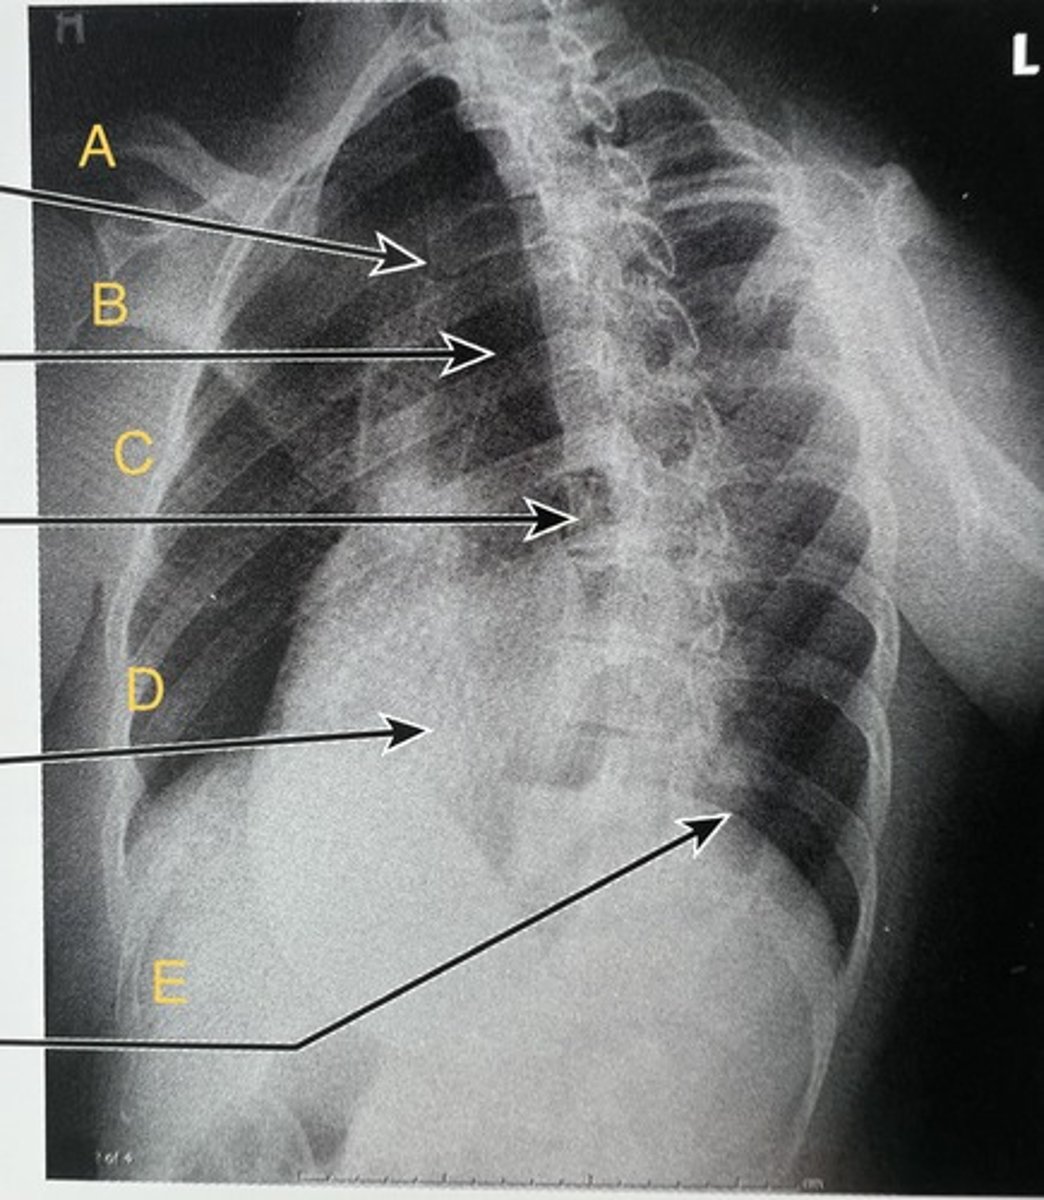

A.

Trachea

B.

Vertebral body

C.

Heart

D.

Diaphragm

E.

Oblique ribs

What position?